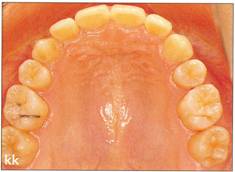

Fi 545e45f gs 5-8kk to Fi 545e45f g 5-8nn Two years 6 months after transplantation. |

|

Fi 545e45f g 5-800 Two years 6 months after transplantation. Normal appearance of periodontal ligament and lamina dura is observed. |

Fi 545e45f g 5.8pp Fi 545e45f ve years after transplantation. |